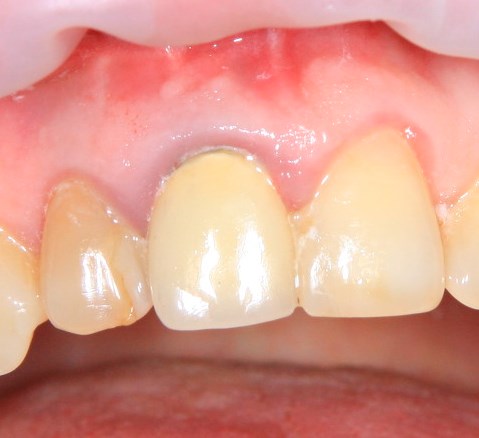

Немедленная имплантация — оптимальное решение в любой клинической ситуации